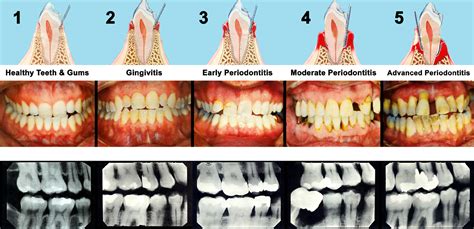

Wondering what does gingivitis look like? Discover the common signs of early gum disease, including swollen, red, and bleeding gums. Learn how to identify symptoms, understand the causes of gingival inflammation, and find effective oral hygiene tips to restore your dental health and prevent periodontitis before it progresses. Protect your smile today with these expert insights.